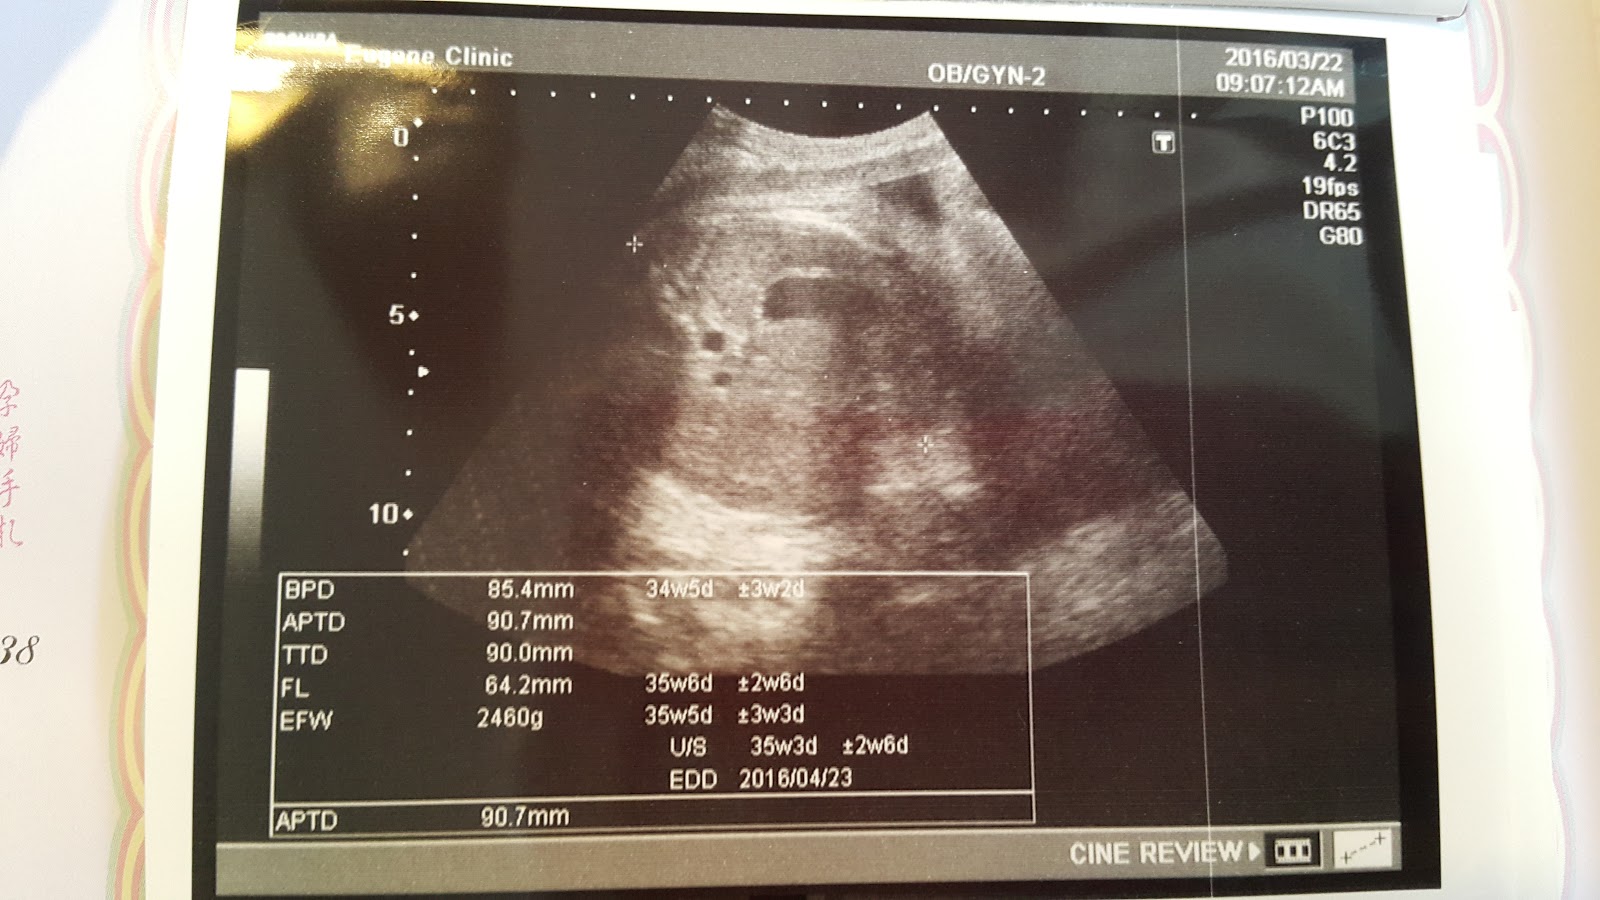

Haru比2週前多了320g,目前是2460g

長的很好,預計出生時間那時大約3000左右

預產期是4月21日,每次產檢Haru的各項產檢數據都落在預產期的時間